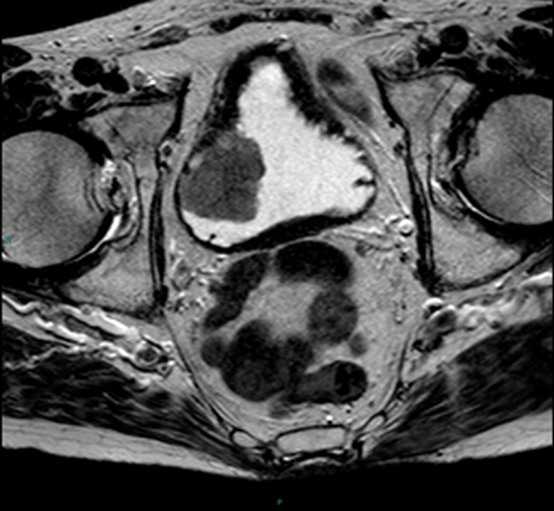

📌صورة الرنين المغناطيسي (MRI)

◀️التصوير بالرنين المغناطيسي MRI